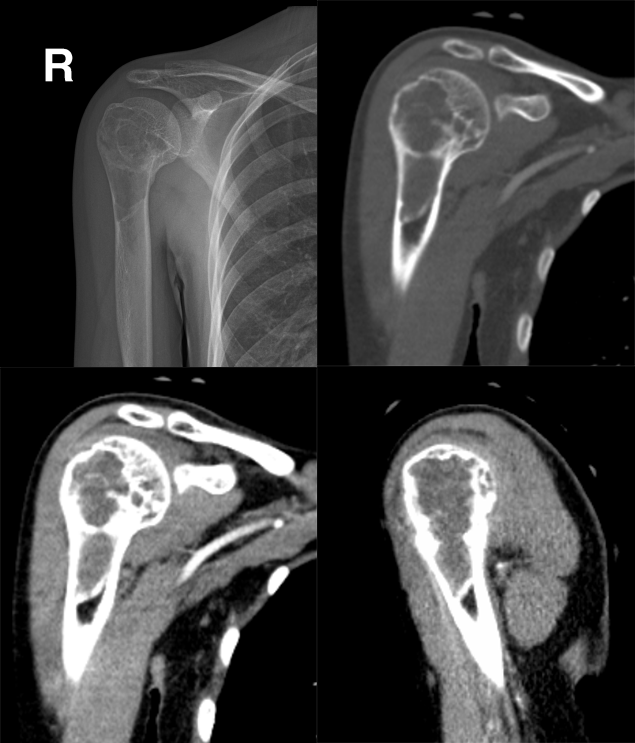

CASE 2 医学百科网 | YxBaike.Com

女,21 岁,右肩部疼痛、肿胀、活动受限半年 医学百科网 | YxBaike.Com

医学百科网 | YxBaike.Com 免疫组化示:「右肱骨近端病灶活检标本」:动脉瘤样骨囊肿 医学百科网 | YxBaike.Com